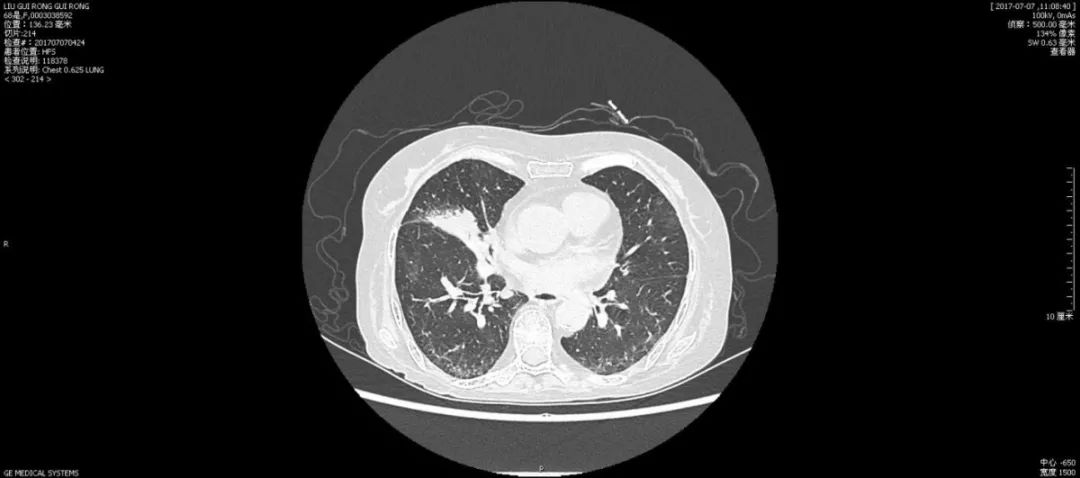

患者68岁女性,因“间断乏力伴血肌酐升高2月”于2016年11月诊断为“ANCA相关性血管炎、小血管炎肾损害”,给予甲泼尼龙片(40mg qd)和环磷酰胺治疗,2017年4月20日停用环磷酰胺。继续口服激素治疗。5月11日患者因咳嗽咯痰伴发热就诊,查胸部CT(图1-1)

住院期间(2017年7月21日)患者出现咳嗽咯痰加重,伴白细胞升高、呼吸功能衰竭、代谢性酸中毒、电解质紊乱,胸部CT提示左肺下叶新出现渗出影伴双侧胸腔积液。(图1-3)